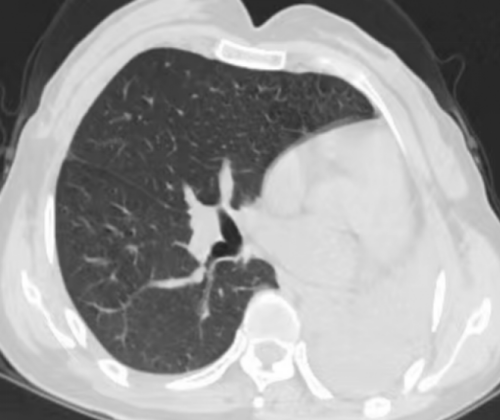

吴丽胸部CT显示左肺“消失”

“为了找回‘消失’的肺,我们给她安排了胸部增强CT。发现其左主支气管狭窄、远端及各叶段支气管闭塞并左肺团片影及肺不张。”据91短视频

(南华大学附属长沙中心医院)呼吸与危重症医学科内镜诊疗部副主任医师刘超群介绍。为进一步明确病因,完善支气管镜检查,检查见左主支气管瘢痕闭塞,未见远端管腔。据了解,吴女士三年前被确诊为支气管结核、支气管狭窄,医生开了抗结核药物治疗,并叮嘱她要定期复查。但症状明显好转后,吴丽就放松警惕,没有规律治疗了。结合患者既往病史,诊断为支气管结核(管腔闭塞型)、左肺完全不张。